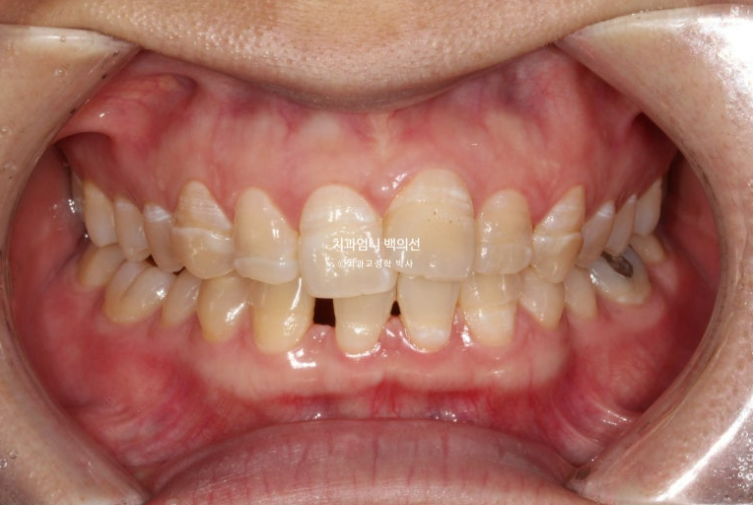

환자분은 교정으로 고치고자 하는 것이 오직 배열과 벌어진 공간 두 가지 였습니다.

하지만 윗니 돌출도 있어서 상악 소구치 2개 발치교정 쪽으로 치료계획을 세웠습니다.

아래는 치아가 원래 2개가 없으니 상악만 교정발치 2개를 하면 균형도 맞아지고 상악에만 국한된 덧니와 돌출 문제도 같이 해결할 수 있습니다.

단 이경우 아래 송곳니는 결손된 앞니 자리로 끌어와 앞니로 대체하고 아래 작은어금니를 송곳니 자리로 끌어와 송곳니로 대체합니다.

이렇게 하면 어금니도 정확한 1급 교합관계 달성이 가능합니다.

클리피씨 교정 선택하셨습니다.

중심선은 정확히 맞고 앞니 교합도 좋습니다.

파란화살표는 사실 앞니가 아니라 송곳니 입니다.

어금니 교합관계는 정확히 1급입니다. 송곳니 자리에 있는 파란 화살표는 사실 송곳니가 아니라 첫번째 작은어금니입니다.